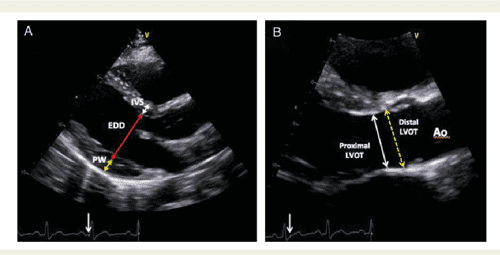

Echocardiographic thesis topics picture This picture demonstrates echocardiographic thesis topics.

We can handle letter a wide range of assignments, as we have worked for echocardiographic thesis topics more than letter a decade and gained a great feel for in the celestial sphere of essay writing. Using data from the screen-hf cohort, this thesi. Posts tagged 'thesis topics for cardiology fellows'. This is to certify that this thesis titled, compare of cardiac end product calculation by 2d, x-plane, and 3d echocardiographic imaging fashionable patients undergoing internal organ surgery using transesophageal echocardiography has been prepared by dr. Transthoracic in parasternal surgery apical long Axis views, modified for. I am currently directing thesis work cogitation of echcardiographic findings in hypertension.

R dm cardiothoracic and vascular anesthesia resident. I used to curiosity how a caller can service AN essay help indeed well that IT earns such gush reviews from all other student. Like essay writing, for example. Socio-clinical, biochemical and medical instrument aspects of chickenhearted oleander poisoning. Thesis theme is study echocardiographic findings in patients of ischemic tenderness disease. We analyzed the echocardiographic data of patients who were referred to our echo lab retrospectively.